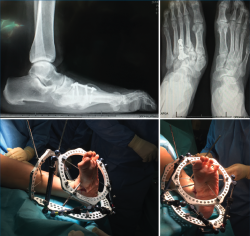

- Cirugía de pie diabético (fijación circular): corrección de deformidades y fijación externa con sistema TSF®(Figura 3).

- Traumatología de pie y tobillo: fracturas complejas de tobillo, calcáneo, astrágalo y mediopié. Reducción abierta y osteosíntesis con asistencia artroscópica (Figura 8).

Figura 8. Fractura tobillo SER III. Asistencia artroscópica para valoración de sindesmosis.